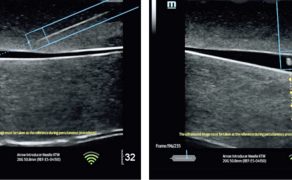

Jednym z najbardziej przełomowych elementów tej transformacji jest rozwój systemów automatycznego labelingu, czyli kolorowego kodowania struktur anatomicznych w czasie rzeczywistym. Rozwiązania te, oparte na algorytmach uczenia maszynowego i głębokich sieciach neuronowych (m.in. architekturze U-Net), umożliwiają automatyczne rozpoznawanie i oznaczanie kluczowych struktur, takich jak nerwy, naczynia, mięśnie, powięzi czy opłucna, przy użyciu czytelnego kodu kolorystycznego. W efekcie obraz ultrasonograficzny przestaje być jedynie płaską reprezentacją anatomii, a zaczyna pełnić funkcję interaktywnego interfejsu informacyjnego (6).

Z perspektywy anestezjologii szczególne znaczenie ma zastosowanie labelingu w regionalnych technikach znieczulenia oraz w procedurach wykonywanych pod kontrolą ultrasonografii. Kolorowe oznaczenie struktur pełni wówczas funkcję swoistego head-up display, który w czasie rzeczywistym wspiera orientację przestrzenną operatora i zmniejsza ryzyko przypadkowego uszkodzenia struktur krytycznych. Badania wskazują, że tego typu rozwiązania mogą skracać czas wykonywania procedur, zwiększać ich bezpieczeństwo oraz zmniejszać zależność jakości zabiegu od doświadczenia operatora (2, 6).

Naturalnym uzupełnieniem systemów labelingu są technologie umożliwiające precyzyjną identyfikację i śledzenie położenia igły w czasie rzeczywistym. W klasycznej ultrasonografii prowadzenie igły pod kontrolą obrazu wymaga jednoczesnej kontroli osi wiązki ultradźwiękowej, kąta wkłucia oraz relacji igły do struktur krytycznych, co stanowi istotne obciążenie poznawcze nawet dla doświadczonych operatorów. Nowoczesne systemy nawigacji igły wykorzystują magnetyczną identyfikację jej położenia względem płaszczyzny obrazowania, dostarczając jednoznacznej informacji zwrotnej dotyczącej trajektorii wkłucia i położenia końcówki igły (1).

Z klinicznego punktu widzenia rozwiązania te pełnią rolę aktywnego wsparcia orientacji przestrzennej, szczególnie w regionalnych technikach znieczulenia, kaniulacjach naczyń zarówno centralnych, jak i obwodowych oraz procedurach wykonywanych w bezpośrednim sąsiedztwie struktur krytycznych. Połączenie magnetycznej identyfikacji igły z labelingiem struktur anatomicznych tworzy spójny ekosystem interpretacyjny, w którym lekarz otrzymuje odpowiedź zarówno na pytanie „co widzę?”, jak i „gdzie znajduje się igła i dokąd zmierza?” (1, 6).